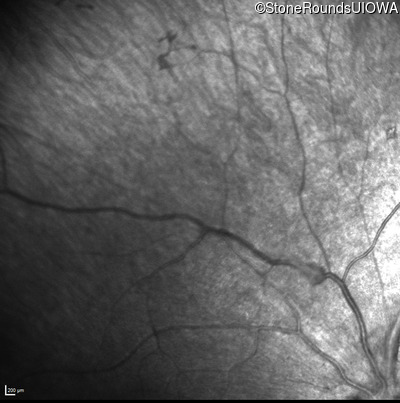

Infrared Fundus Photograph - Left - No Light Perception

Exemplar